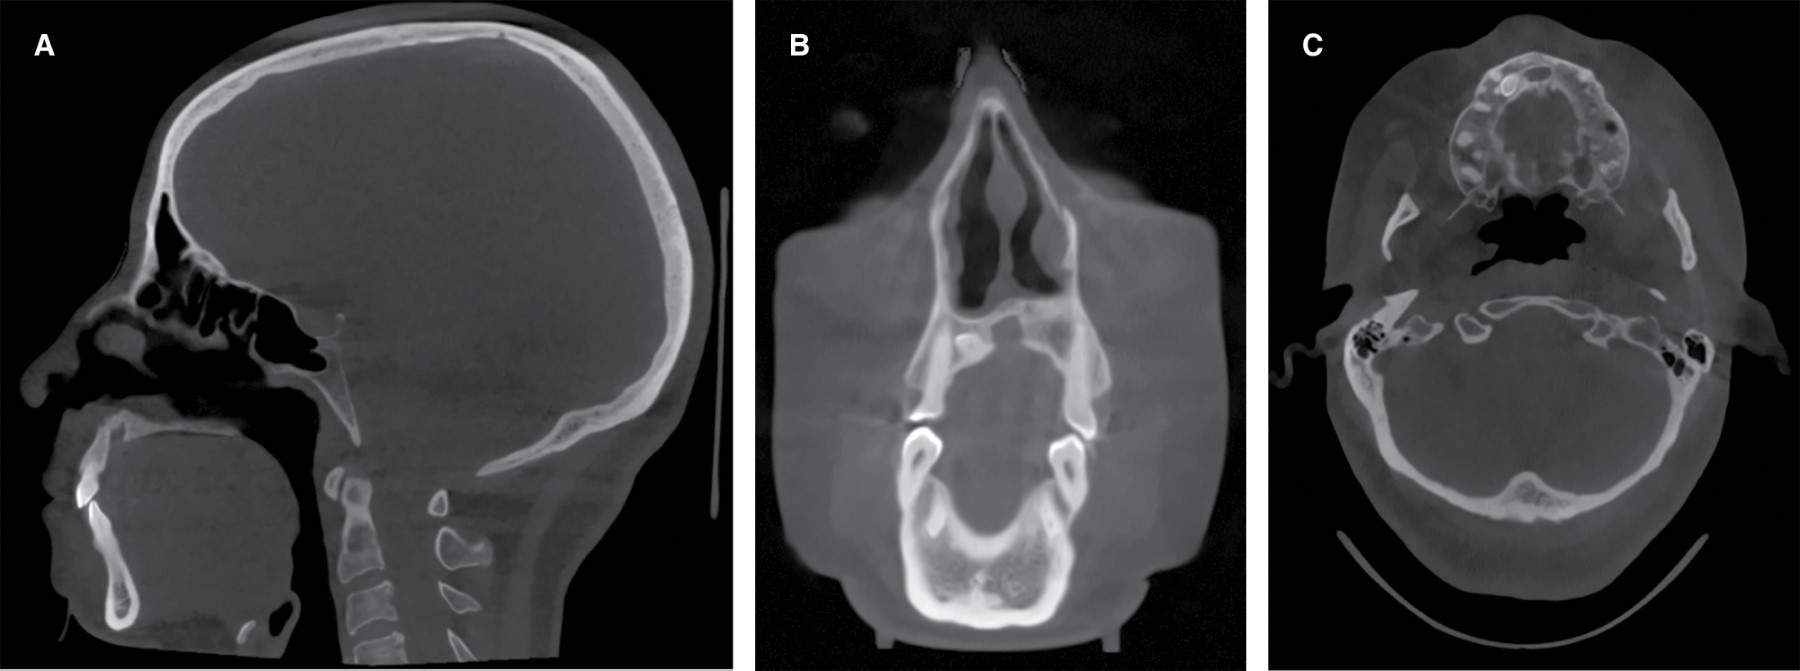

Junto al equipo de otorrinolaringología se programa cirugía conjunta en dos tiempos bajo anestesia general, utilizando el acceso quirúrgico de cirugía nasal para acceder a diente supernumerario ubicado en el tabique nasal. En primera instancia se realiza reducción y lateralización de cornetes nasales inferiores con radiofrecuencia CELON y espéculo de Killian, posteriormente se efectúa incisión medio columelar en V invertida con disección de columela, punta nasal y dorso abierto. Se expuso el borde anterior y premaxila donde se identifica ubicación de mesiodens a la izquierda y posterior a la espina nasal anterior, exponiendo mesiodens a través de osteotomía con instrumental rotatorio, luxación y avulsión con elevador recto (Figura 3). Se extirpan las porciones desviadas del tabique osteocartilaginoso, aprovechando el tejido óseo para su uso como injerto autólogo, y se reconstruye el lecho quirúrgico en la ubicación original del mesiodens. Finaliza la cirugía de rinoseptoplastia funcional, turbinectomía y desinclusión del mesiodens sin incidentes.

Se realiza un control postquirúrgico a las dos semanas donde la paciente se presenta con buena evolución, con dorso nasal alineado, tabique nasal en línea media sin hematoma y cornetes pequeños, relatando respirar bien por ambas fosas nasales y un control con imagen a los nueve meses (Figura 4) donde se observó una correcta cicatrización del tejido óseo.

Figura 3

Figura 4